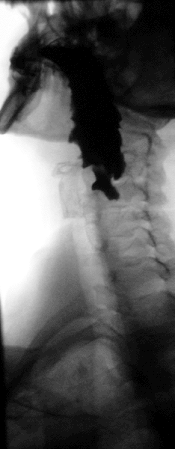

Contraststof bij röntgenfoto's

Doordat barium een relatief zwaar en groot atoom is (Z = 56), absorbeert het beter röntgenstraling dan het lichaam. Daarom wordt bariumsulfaat gebruikt als contraststof (bariumpap) bij het maken van röntgenfoto's van wekere delen (organen) van het lichaam. De patiënt neemt dit bariumsulfaat in als een suspensie. Omdat bariumsulfaat geen giftige verbinding is, kan dit geen kwaad in het menselijk lichaam. Bariumsulfaat is niet giftig omdat het - in tegenstelling tot veel andere bariumverbindingen die wel giftig zijn - vrijwel niet oplost in water. Daardoor kan het niet in het metabolisch systeem van het lichaam worden opgenomen.